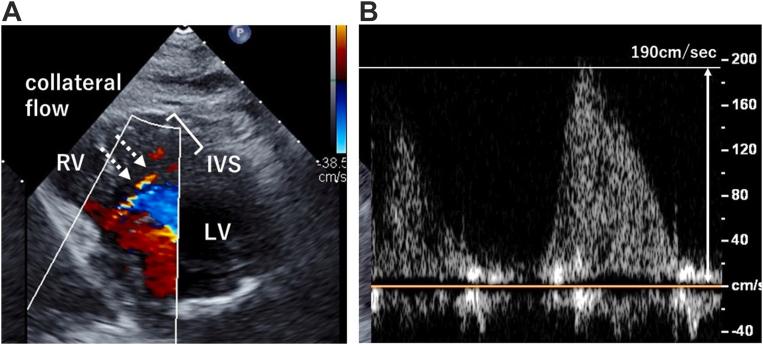

• ALCAPA can be diagnosed for the first time in older adults. • Collateral coronary blood flow from the RCA leads to RCA dilatation. • Consider ALCAPA with reduced LVEF, bright papillary muscles, MR, and RCA dilatation. • Color and spectral Doppler is useful to assess perioperative coronary arterial flow.

摘要

• 成人也可能首次被诊断出左冠状动脉起源异常。

• 来自右冠状动脉的冠状动脉侧支血流导致右冠状动脉扩张。

• 对于左心室射血分数降低、乳头肌显影、二尖瓣反流和右冠状动脉扩张的情况,应考虑左冠状动脉起源异常。

• 彩色及频谱多普勒有助于评估围手术期冠状动脉血流。